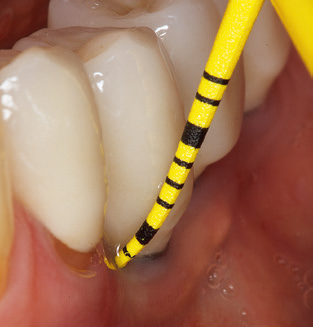

Das aktuelle Arbeitskonzept für die UPT

Die Aktualisierung der Anamnese stellt im Rahmen der UPT eine zentrale Maßnahme dar, sie sollte mindestens einmal jährlich erfolgen. Sie dient dazu, mögliche neue Risikofaktoren zu erkennen und zu dokumentieren. Vor allem dann, wenn ein Patient langjährig betreut wird, ist es wichtig, zu erfahren, ob sich patientenspezifische und allgemeinmedizinische Risikofaktoren verändert haben. Hier sollte an erster Stelle an ein erhöhtes Risiko durch Diabetes gedacht werden, aber auch andere allgemeinmedizinische Erkrankungen (kardiovaskuläre Erkrankungen und Neoplasien) können aufgrund der erfolgten Therapien und der notwendigen Medikamenteneinnahme zu einem veränderten Risikoprofil führen. Das Update der Anamnese ist also auch im Rahmen der UPT sehr wichtig, um gegebenenfalls aufgrund eines veränderten Risikoprofils eine Veränderung des Behandlungsintervalls zu veranlassen. Im nächsten Schritt ist es wichtig, der Diagnostik besondere Aufmerksamkeit zu schenken. Die Instrumentation ist zwar ein zentraler Bestandteil der UPT, in keinem Fall sollte sie aber Bestandsaufnahme und Dokumentation verdrängen. Für die Diagnose ist dabei der parodontale Befund unerlässlich, eine Zunahme der Sondierungstiefen und eine Erhöhung des BOPIndex sind zentrale Indikatoren für eine Progression parodontaler und periimplantärer Erkrankungen. Zum Erheben der benötigten Daten darf daher nicht davor zurückgeschreckt werden, auch Implantate zu sondieren. Dabei ist es wichtig, dass hierfür millimeterskalierte PARSonden verwendet werden. Für die Sondierungsbefunde an natürlichen Zähnen haben sich seit Jahrzehnten metallische Sonden bewährt. Bei Implantaten ist die Herausforderung für das Erheben korrekter und reproduzierbarer Sondierungsbefunde größer. Da es durch die Diskrepanz von Implantatdurchmesser und Kontur der Suprakonstruktion regelmäßig zu einer Überkonturierung der Suprastruktur kommt, sind für Sondierungen an Implantaten flexible, aber dennoch millimeterskalierte Son den sehr sinnvoll (z. B. Colorvue Kit PCV11KIT6, HuFriedy; Abb. 4).

Das Erheben eines kompletten PAR Status sollte bei Patienten ohne besondere Risikofaktoren mindestens einmal pro Jahr erfolgen. Bei Vorliegen mehrerer Risikofaktoren (Diabetes, Rauchen etc.) kann ein engmaschigeres Monitoring (halbjährlich) sinnvoll sein.